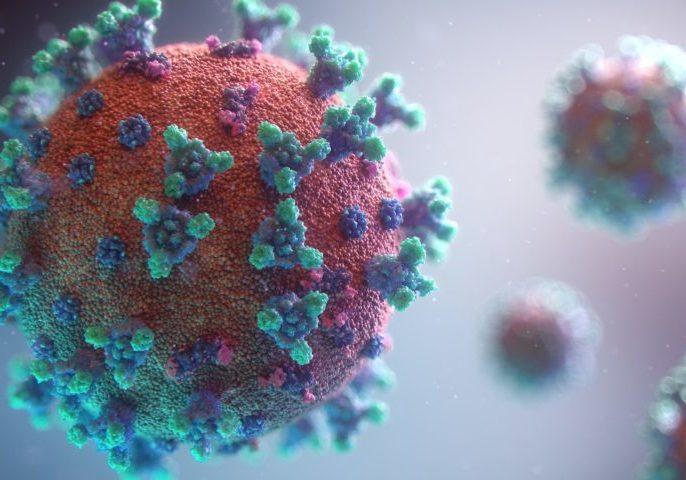

Cientistas franceses alertam que aquecimento global pode despertar vírus ‘zumbis’